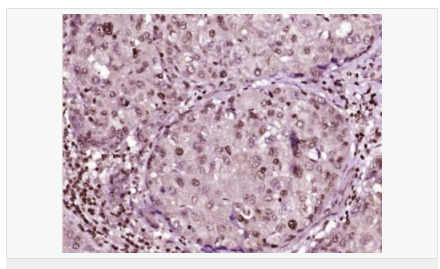

產品應用ELISA=1:5000-10000 IHC-P=1:100-500 IHC-F=1:100-500 Flow-Cyt=1μg/Test ICC=1:100 IF=1:100-500 (石蠟切片需做抗原修復)